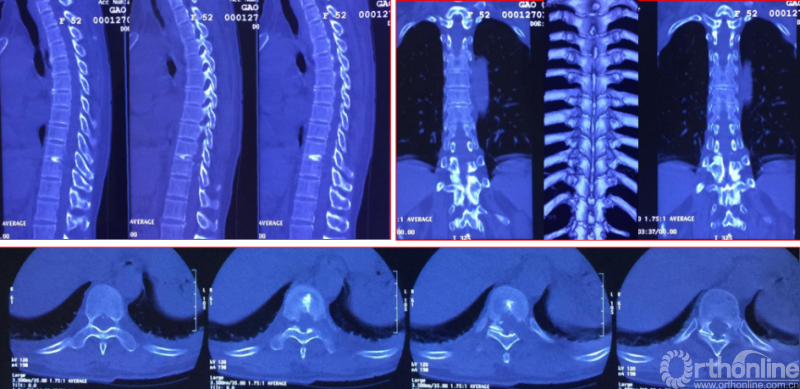

Case1:胸椎黄韧带钙化可视化的治疗

手术资料

择期分次手术资料